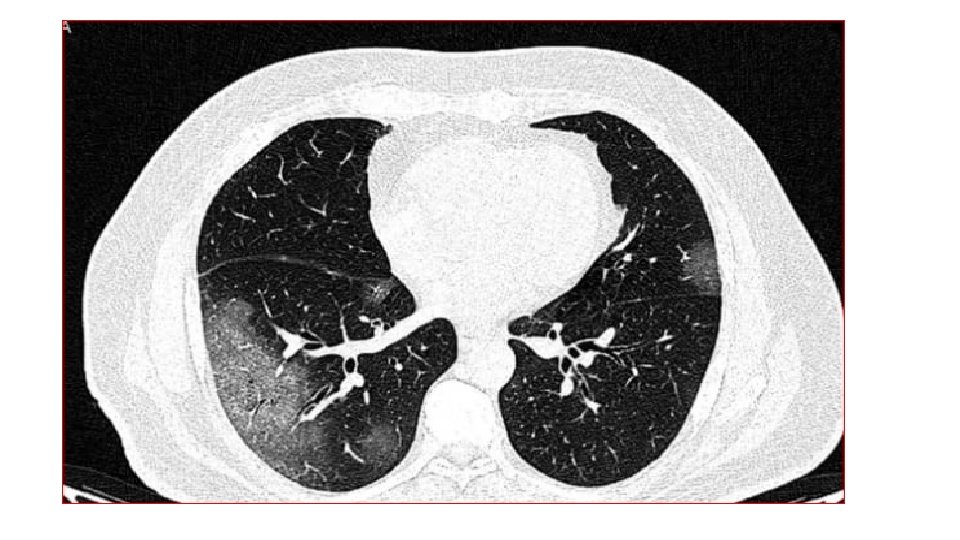

Chest X-ray An X-ray : look for signs of inflammation in chest. If inflammation is present, the X-ray can also inform about its location and extent.

In COVID-19 pneumonia Leukopenia in ~70% of hospitalized patients. LDH may be modestly elevated. LFTs elevated more commonly than in typical Community-Acquired Pneumonia cases. Chest CT may show ground-glass opacities that may evolve into consolidation or ARDS. Findings appear to peak at 10 d of illness, resolution begins after day 14. CT may show lung findings (such as ground-glass opacities) before the development of symptoms. Among hospitalized patients, about one-third need to be in the ICU/intubated with an ARDS picture. Elevations in IL-6 (> 40– 100), CRP (> 10 x normal), ferritin (> 1000) suggested correlating with a cytokine release syndrome-like picture and impending ARDS.